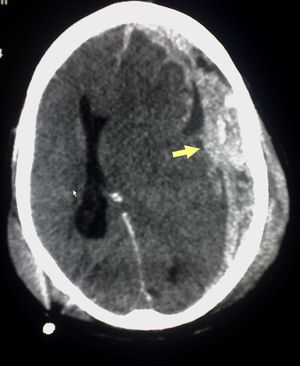

| Appearance on CT | Biconvex lens | Crescent-shaped |

يعتمد رئيساً على تصوير الدماغ (التصوير الطبقي المحوري والرنين المغنطيسي MRI)، وفيه يظهر النزف عادة على شكل تجمع هلالي بين الجمجمة والدماغ.